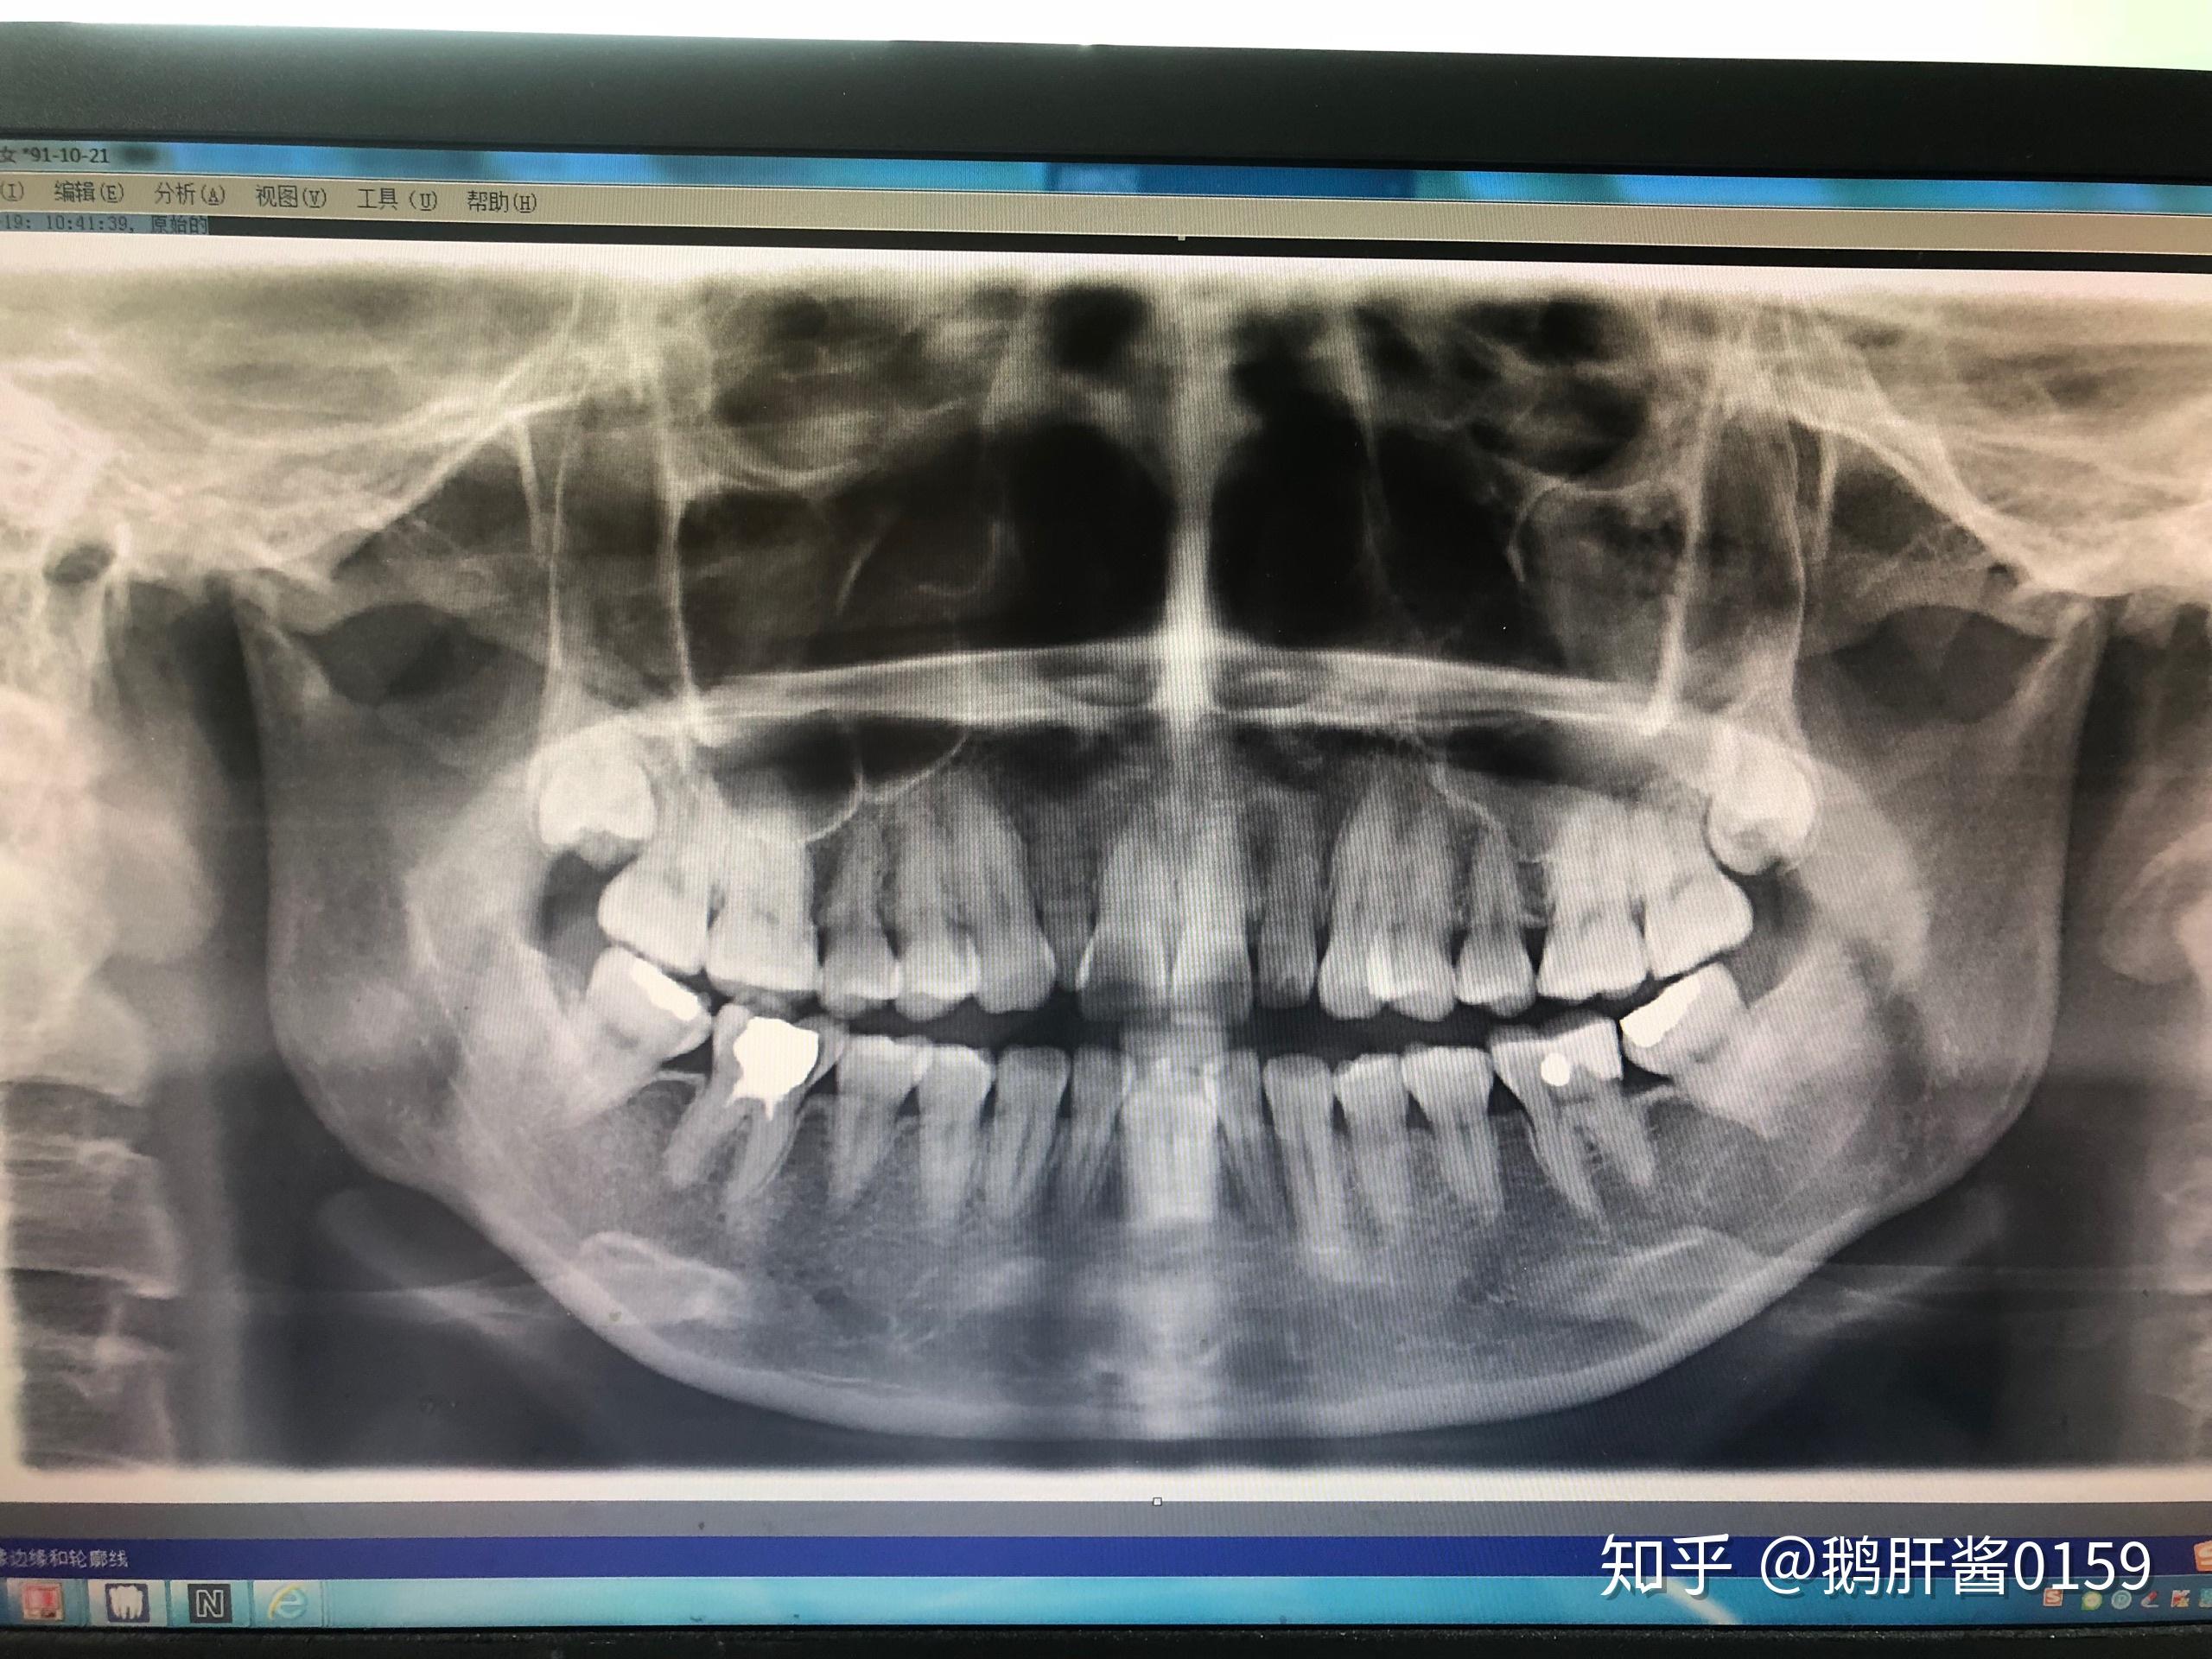

20年深圳大学总医院朱医生诊断:左右两边关节盘不可复性移位,髁突吸收

曲面体层片示:双侧颞下颌关节髁突严重吸收,38,48近